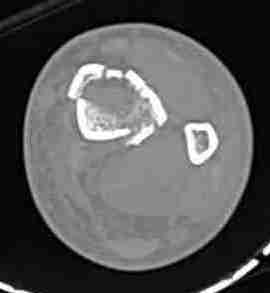

При высокоскоростных переломах редко можно встретить изолированную травму пилона, и в моей практике изолированные травмы большая редкость, поэтому, как дополнение к обсуждаемой теме, решил представить свежий, двухдневной давности случай.

Предыдущей сменой до 4:00 утра по поводу открытого перелома бедра, тибиал плато, пилон и надколенника сделана операция.

Пострадавшему 21 г., травма скоростная, после I&D с расширением раны, на бедре сделана операция ретроградным интрамедуллярным штифтом, остеосинтез с частичной резекцией надколенника и ушивание собственной связки.

КТ пилона имеем.